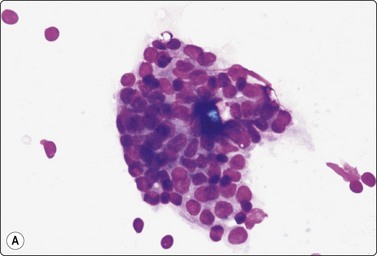

Breast tissue in pregnancy and lactation (Fig. 7.8)

image image image

Fig. 7.8 Lactating breast

Dispersed acinar cells with abundant pale and fragile cytoplasm, rounded nuclei and prominent central nucleoli; background of lipid secretions (A, MGG, HP; B, H & E, HP oil); (C) Corresponding tissue section (H&E, IP).

Criteria for diagnosis

Cellular smears,

Poorly cohesive, mainly dispersed epithelial cells of acinar type,

Cells have abundant fragile cytoplasm with secretory vacuoles and frayed borders,

Rounded vesicular nuclei and central nucleoli,

Dirty background due to lipid secretion and stripped nuclei with prominent nucleoli,

Single bipolar nuclei difficult to find.

FNB is very useful in reducing surgical intervention to a minimum during pregnancy and lactation. The pattern seen in FNB smears of ‘lumps’ in a pregnant or lactating breast can be problematic to inexperienced eyes and cause concern for malignancy.93,94 Smears are usually cellular. The cells are enlarged and arranged in loose groups or singly. The cells have an abundant fragile cytoplasm, vacuolated and finely granular. Nuclei are round, central, larger than the usual ductular cells, and have distinct small nucleoli (Fig. 7.8B). Some epithelial nuclei are stripped of cytoplasm. Single naked bipolar/oval nuclei are difficult to find. The background of abundant milky secretion with numerous lipid droplets seen as vacuoles is characteristic of actively secreting breast tissue and is the main clue to the diagnosis (Fig. 7.8A).